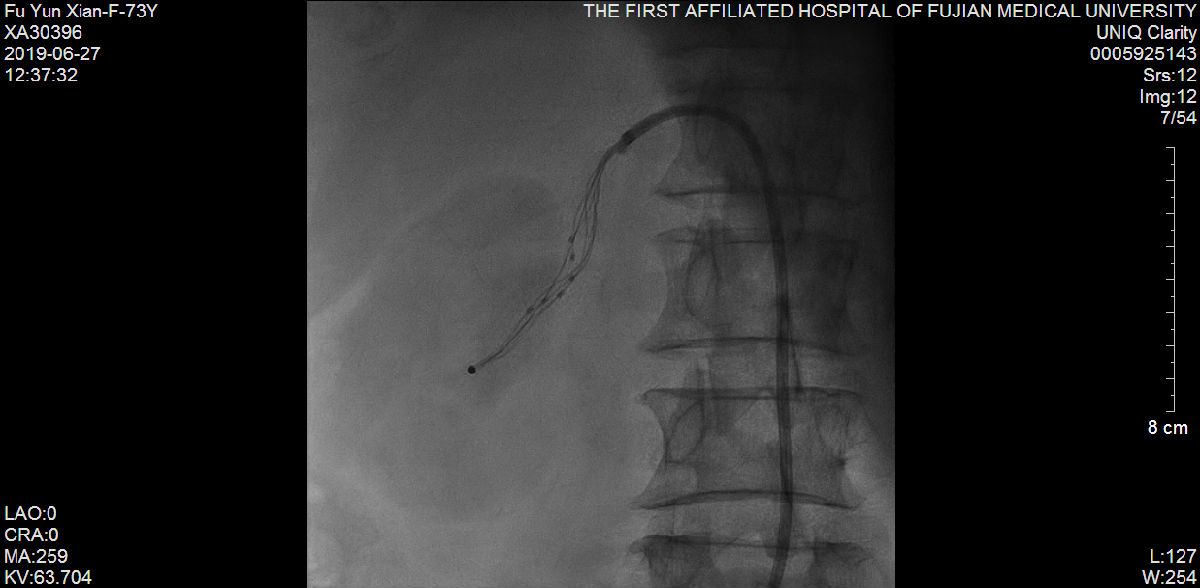

随后,苏津自教授、蔡瀚医师为傅阿姨进行介入手术:肾动脉造影显示双侧肾脏萎缩,右侧肾脏具备进行RDN的条件;而冠状动脉造影显示营养心脏的其中一条主干血管——前降支血管近端99%狭窄伴冠状动脉瘤样扩张。

说干就干,要干就干的漂亮。苏津自团队立即为傅阿姨进行RDN。经过术后3周细致入微的诊疗和护理,傅阿姨血压慢慢下降至160/90mmHg左右,体重也增加到40公斤。随后,柴大军教授、祝江医师在冠状动脉血管内超声(IVUS)的精确定位下,成功为傅阿姨植入一枚支架至前降支血管。前后历经1个月,傅阿姨再也没感觉头痛、胸痛,笑着出院了。